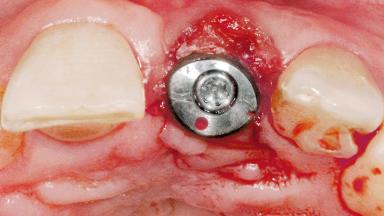

Late Flapless Placement of an Implant in a Maxillary Left Central Incisor Site

A 39-year-old male patient presented with a chief complaint of discomfort and gingival discoloration around his maxillary left central incisor. He was in good general health and was a non-smoker. His past dental history was significant because of the traumatic fracture of tooth 21 in a sporting accident at age 13. Initial dental treatment included endodontic therapy and a full-coverage restoration. The patient became symptomatic 5 years later, when structural failure of the tooth resulted in the dislodgment of the crown. Endodontic retreatment, apical surgery, and post-and-core restoration were performed.

Type of Implants One-Piece

Attachment One-Piece

Placement Protocol Early or late implant placement